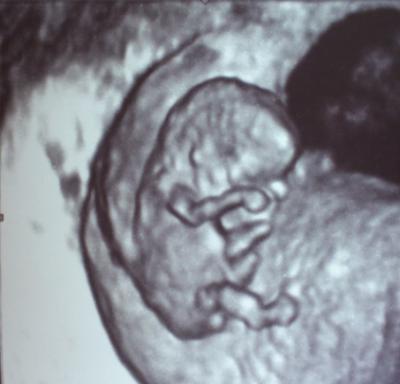

Am Montag konnte man zum ersten Mal einen kleinen Menschen erkennen.. sooo süß

Mami ist verliebt!

Hihi, wirklich schönes Foto! Sieht aus als würde sich Krüme, die Augen reiben!